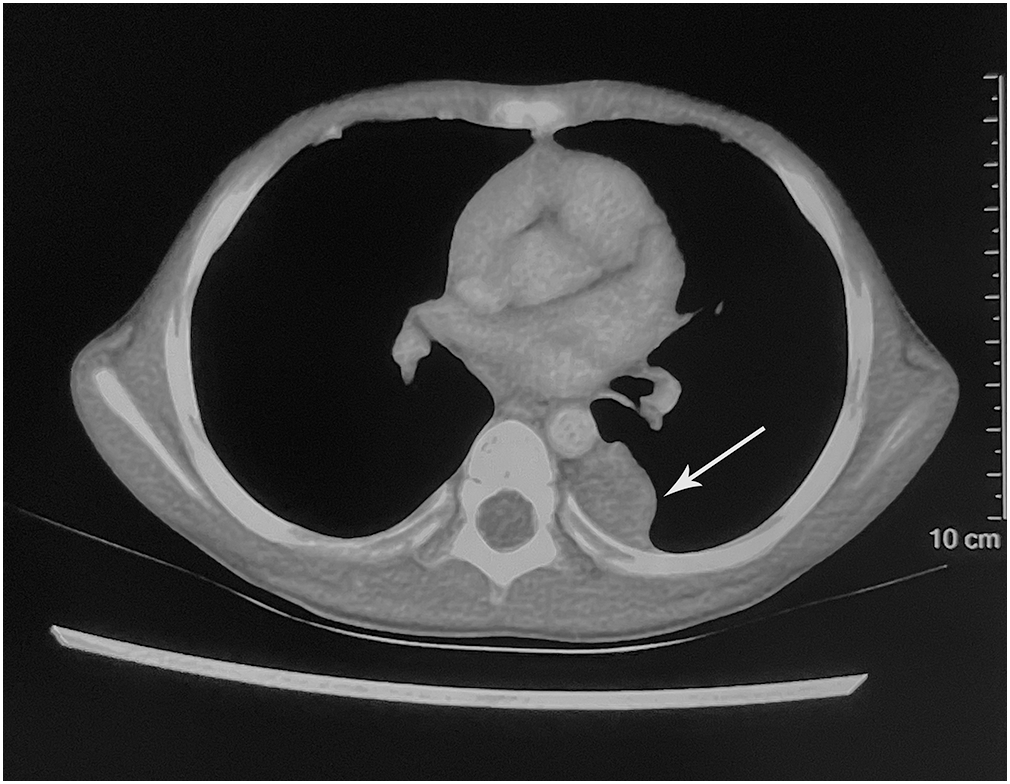

A 4-year-old boy was admitted to a local hospital with a 1-month history of cough and fever and diagnosed with “pneumonia.” Contrast-enhanced computed tomography (CT) revealed a well-defined, heterogeneous soft tissue mass measuring 2.2 cm × 1.9 cm, occupying the left side of the posterior mediastinal paravertebral region (Figure 1).

Figure 1

Imaging findings. The contrast-enhanced computed tomography showed a hypodense mass occupying the left side of the posterior mediastinal paravertebral region (arrow).